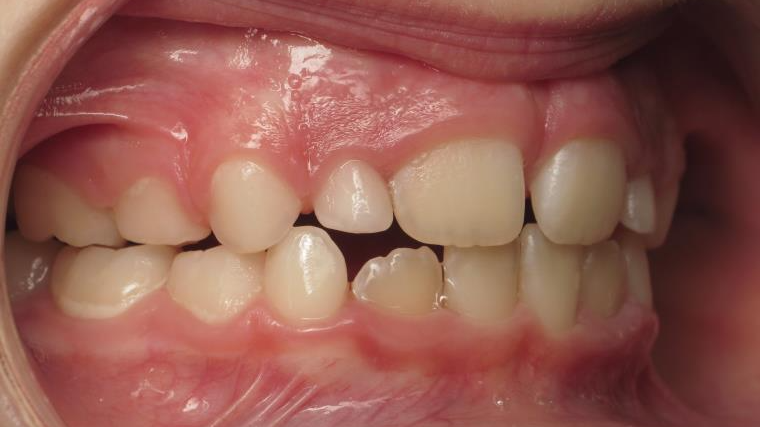

6 décalage sagittal 5 ans

Décalage entre les dents d avant en arrière

surveillance évolution de la dentition pendant 4 ans